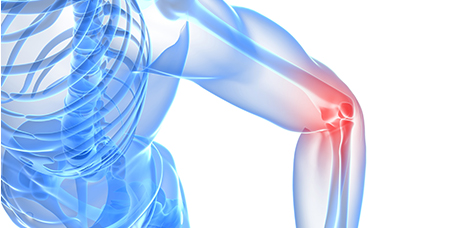

팔꿈치 관절 부위 주요질환

-

테니스 엘보

팔꿈치 바깥쪽 근육힘줄에 염증이 발생한 질환

-

골프 엘보

팔꿈치 안쪽 근육힘줄에 염증이 발생하는 질환